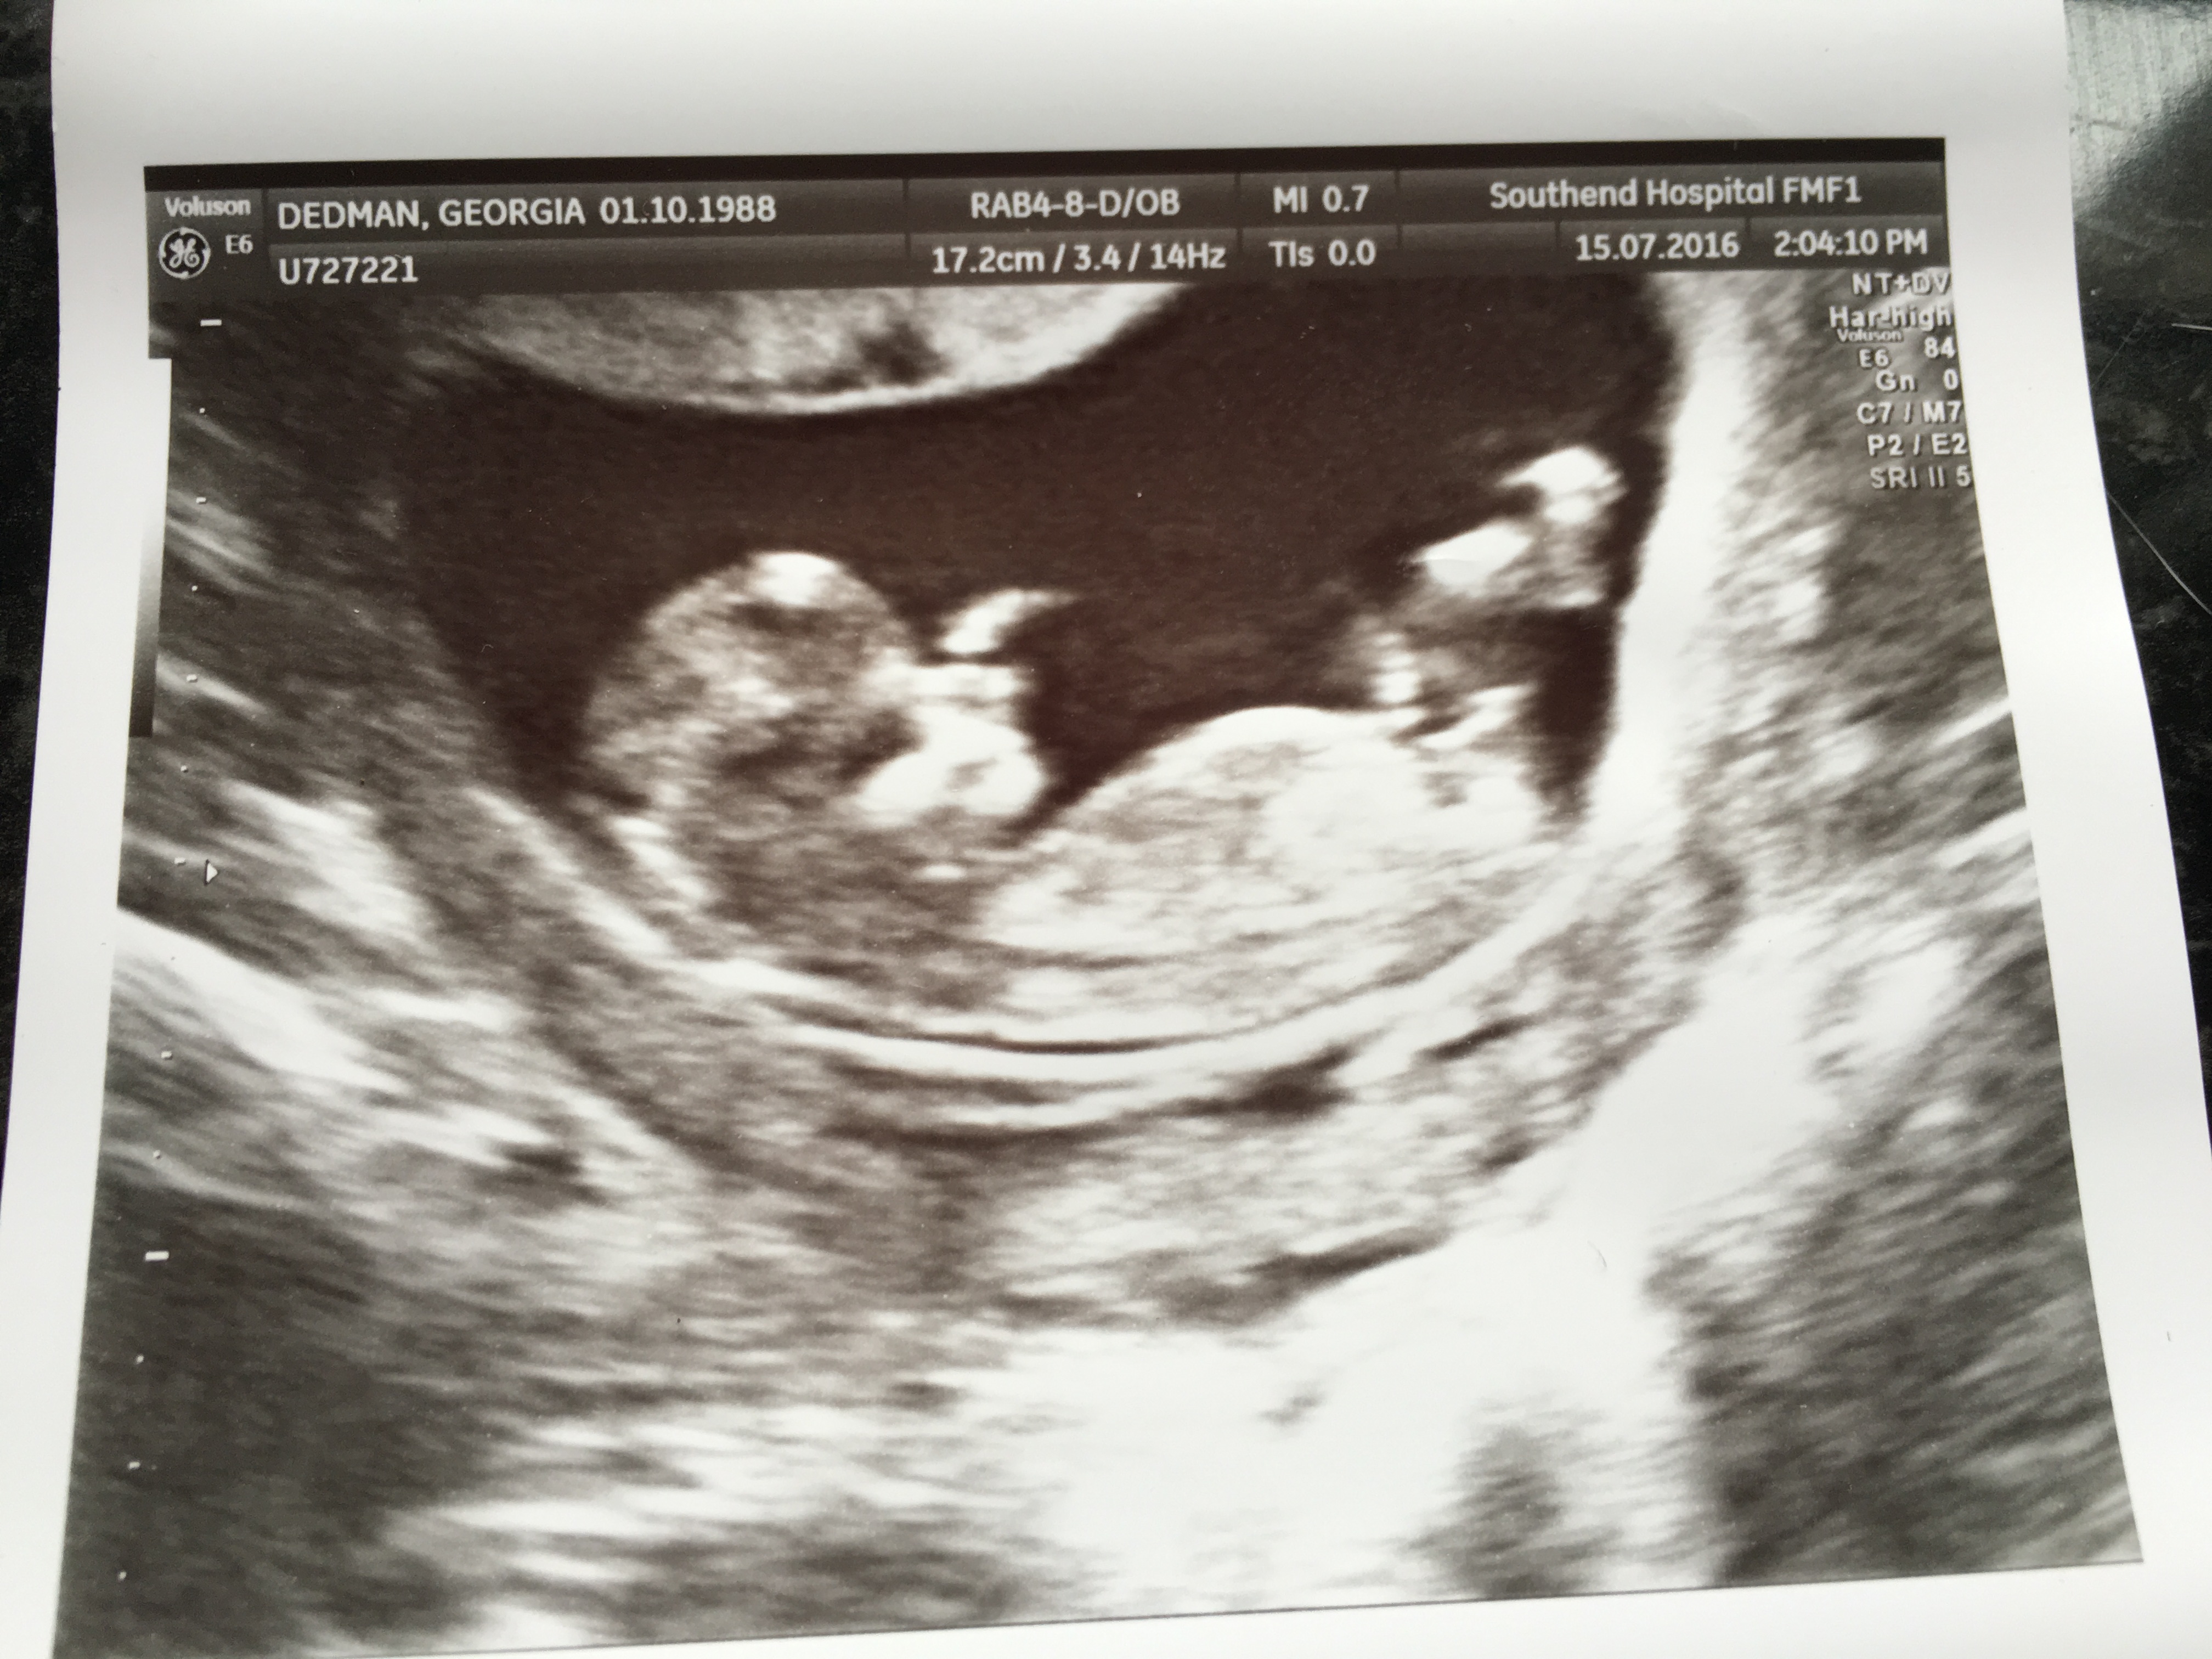

Attachment 32660Attachment 32659

boy!! :DS:

Thanks! I couldn't work out which line was the nub.. Do you think it's the most 'obvious' in the middle?

Confident Boy vote!!!

I agree with the boy vote. :)